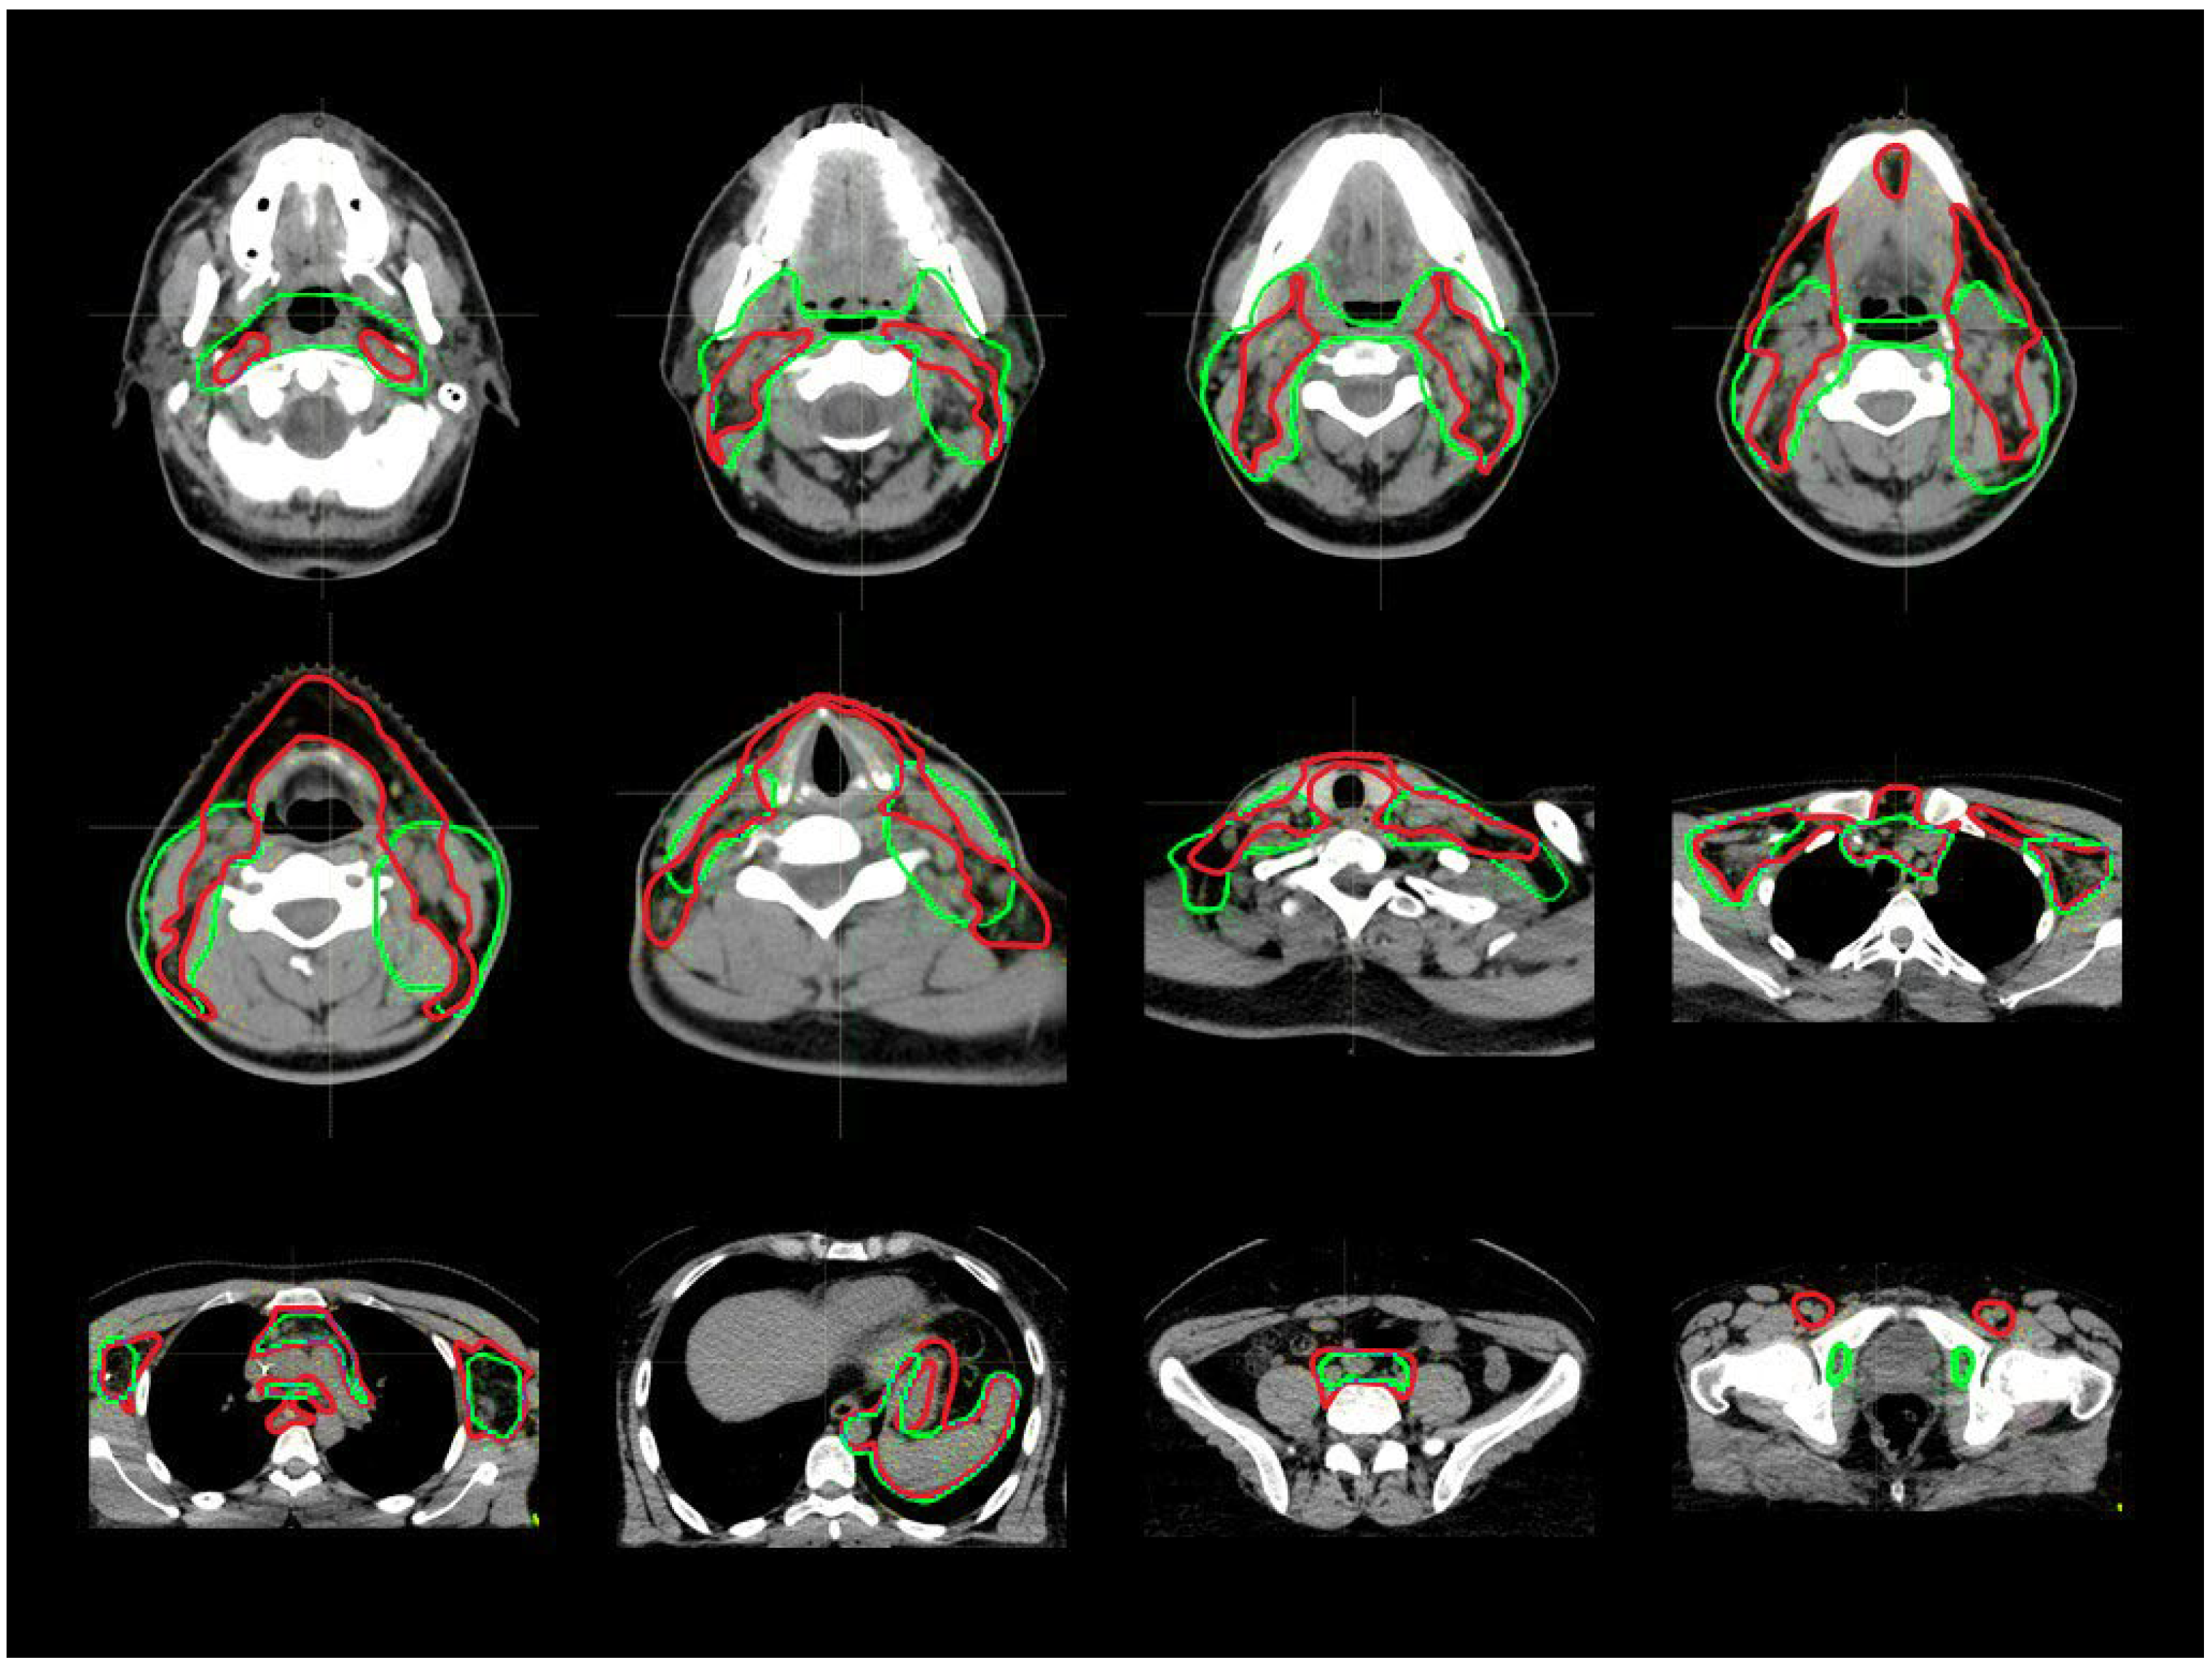

| CTV_LN Comparison | Comparison Abbreviation | Explanation |

|---|---|---|

| GL_RO1 vs. Old | A | After-GL vs. before-GL |

| GL_RO1 vs. GL_RO2 | B | Inter-observer-variability |

| GL_RO1a vs. GL_RO1b | C | Intra-observer-variability |

| LN levels | A | B | C | A vs. B | A vs. C | B vs. C | A | B | C | A | B | C |

| Tot | 0.82 ± 0.09 | 0.97 ± 0.01 | 0.98 ± 0.02 | 0.03 | <0.01 | 1.00 | 0.4 ± 0.2 | 0.1 ± 0.1 | 0.03 ± 0.02 | 7 ± 1 | 2 ± 2 | 1.9 ± 0.3 |

| H&N | 0.69 ± 0.15 | 0.88 ± 0.04 | 0.96 ± 0.03 | 0.27 | <0.01 | 0.13 | 0.5 ± 0.4 | 0.1 ± 0.1 | 0.02 ± 0.01 | 7 ± 7 | 2 ± 1 | 0.9 ± 0.3 |

| Thorax | 0.77 ± 0.15 | 0.97 ± 0.01 | 0.97 ± 0.02 | 0.18 | 0.02 | 1.00 | 0.5 ± 0.5 | 0.1 ± 0.2 | 0.03 ± 0.01 | 6 ± 7 | 2 ± 2 | 1.4 ± 0.5 |

| Abdomen | 0.82 ± 0.08 | 0.98 ± 0.01 | 0.97 ± 0.01 | 0.05 | 0.02 | 0.35 | 0.7 ± 0.4 | 0.1 ± 0.2 | 0.03 ± 0.01 | 8 ± 6 | 1 ± 2 | 1.6 ± 0.6 |

| Pelvis | 0.88 ± 0.09 | 0.96 ± 0.01 | 0.95 ± 0.03 | 0.27 | 0.16 | 0.80 | 0.2 ± 0.2 | 0.1 ± 0.2 | 0.06 ± 0.04 | 3 ± 2 | 1 ± 1 | 1.6 ± 0.5 |